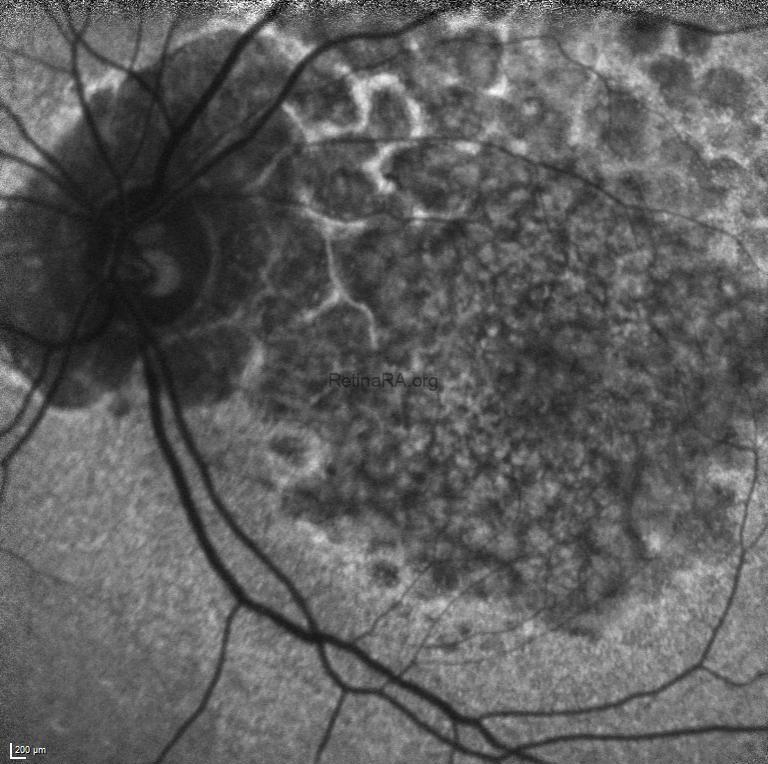

Blue-light macular fundus autofluorescence and wide-field fundus autofluorescence revealed decreased autofluorescence at the macula and increased autofluorescence in mid-peripheral retina.